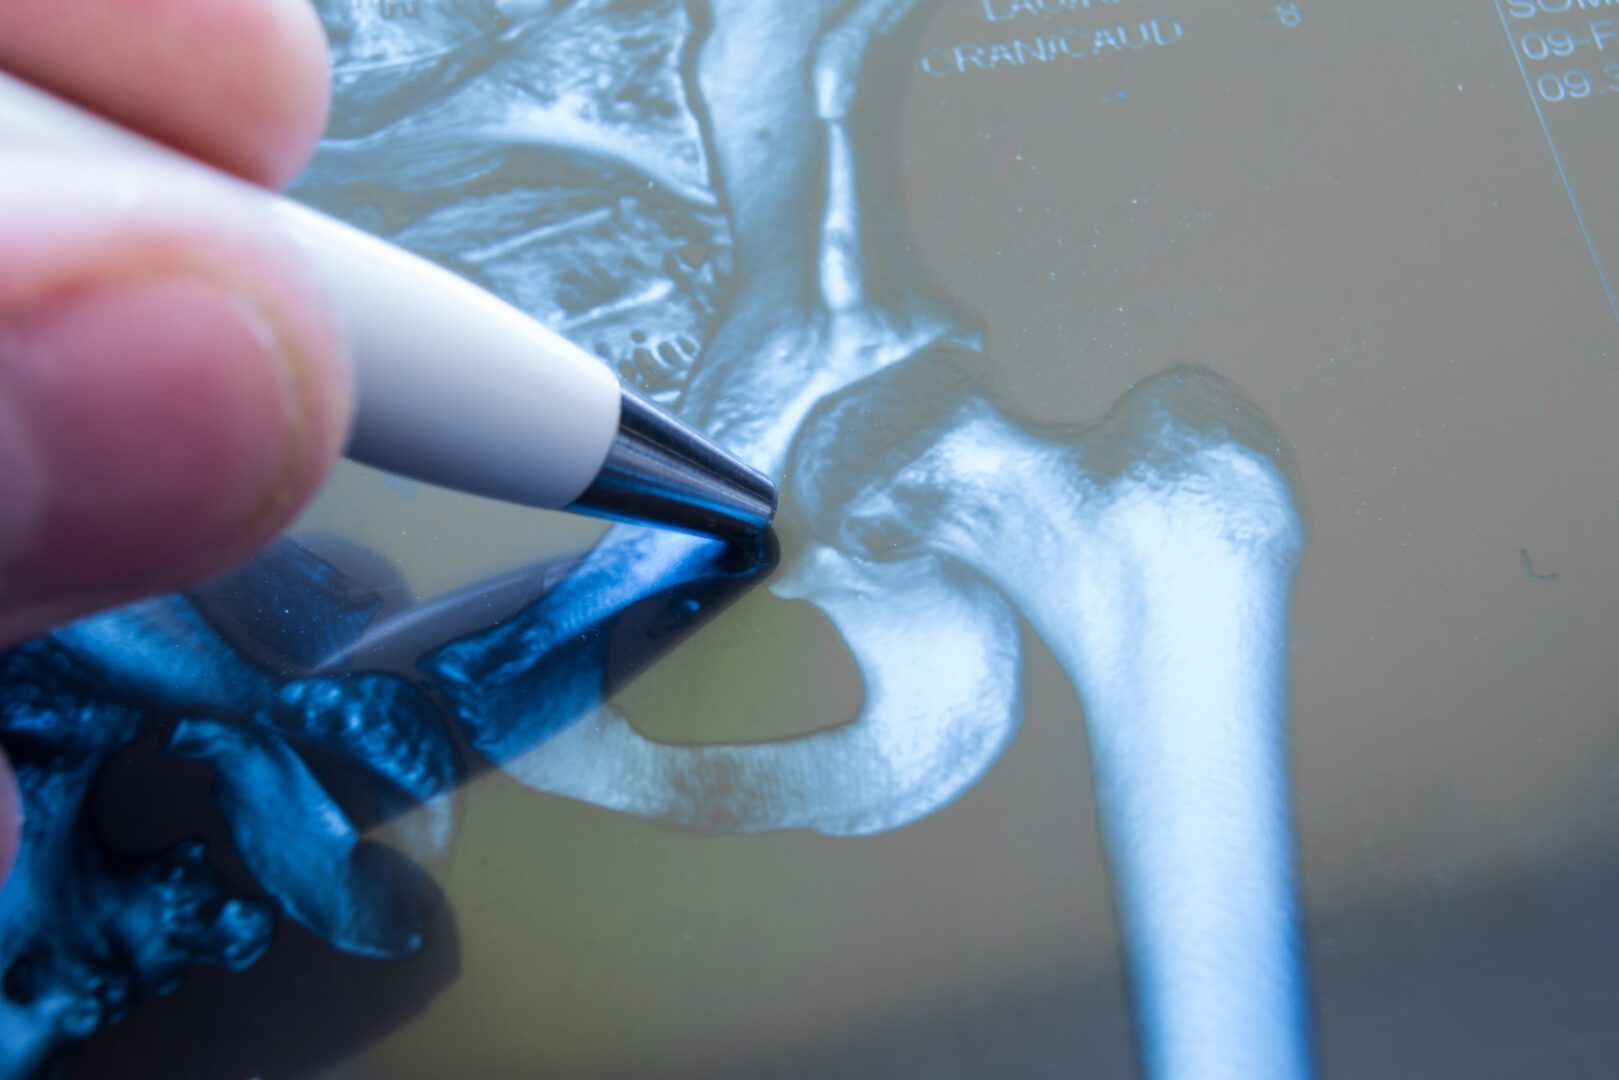

How hip osteoarthritis is diagnosed: X-rays, MRI, and clinical assessment

Diagnosing hip osteoarthritis involves a combination of medical history, a physical examination and imaging tests. Your consultant will ask about your symptoms, lifestyle and any previous hip injuries. They will also assess your range of motion, muscle strength and joint stability during a clinical examination.

X-rays are commonly used to check for changes in joint space, bone shape and the presence of bony growths (osteophytes). In some cases, an MRI scan can provide more detailed images of cartilage, soft tissue and early joint changes that might not appear on an X-ray.